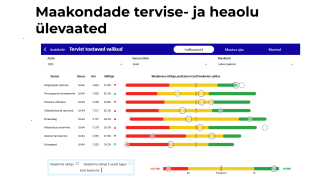

Tervishoiutöötajad kokku (2024)

Elussündinute arv (2025)

Hambaarstide vastuvõtud kokku (2024)

Läbitud viljatusravi tsüklite arv kokku (2025)